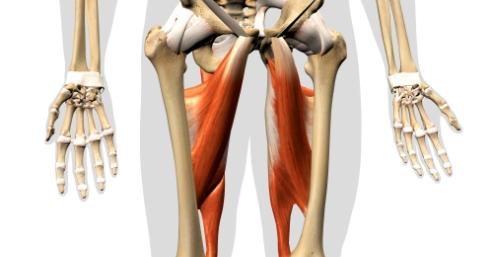

Hip Adductor Muscles Pain

Hip adductor muscles are 3 muscles, which originate from the Ischium bone of the pelvis and insert on the medial aspect of the femoral bone. These muscles are formed by Adductor Magnus, Adductor Brevis, and Adductor Longus. All these muscles ...